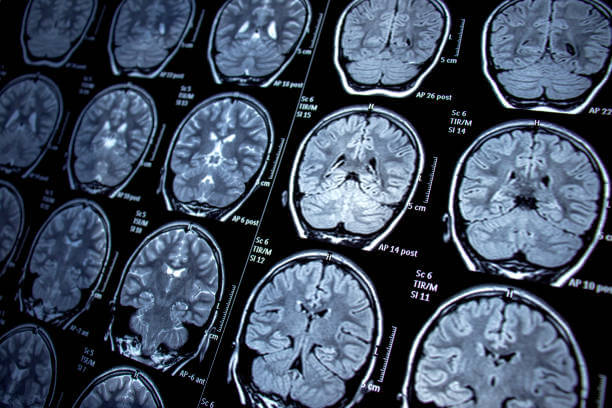

- 뇌전증의 진단을 확인하기 위해 주로 자기공명영상(MRI) 또는 전산화단층촬영(CT) 스캔을 통해 뇌 구조의 이상이나 손상을 확인합니다.